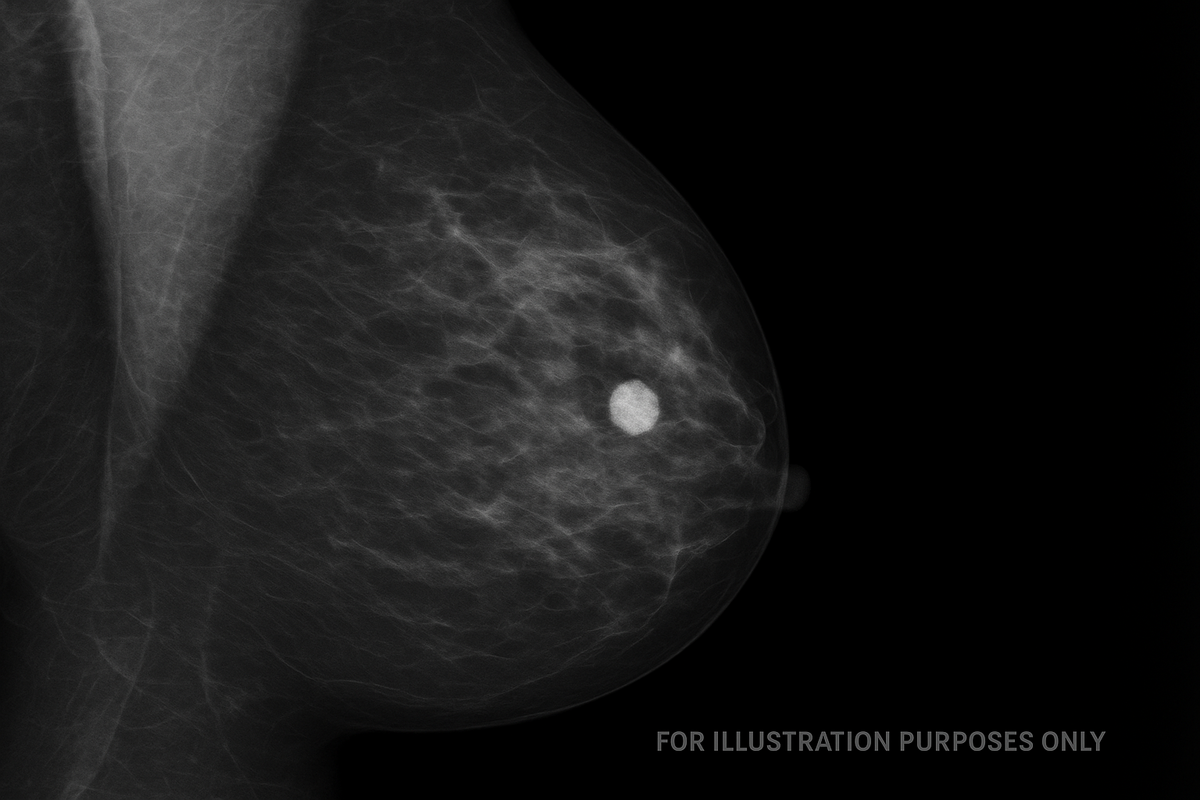

Līguma ietvaros Austrumu slimnīca nodrošinās nepieciešamās telpas un tehnisko atbalstu datu iegūšanai, savukārt LU pētnieki veiks mamogrāfiju attēlu un klīnisko datu sagatavošanu. Kopumā no pacientiem Latvijā plānots iegūt vismaz 200 mamogrāfijas izmeklējumu datus, kuru attēli papildinās Eiropas krūts vēža attēlu datu bāzi.

Savāktie dati kļūs par daļu no plašākas Eiropas iniciatīvas, kas apvieno ES valstis ar mērķi radīt lielāko un kvalitatīvāko vēža attēlu datu kopu pētniecībai. Šāda mēroga datu bāze ļaus attīstīt un validēt jaunus mākslīgā intelekta rīkus, kas var revolucionizēt agrīnu vēža diagnostiku.